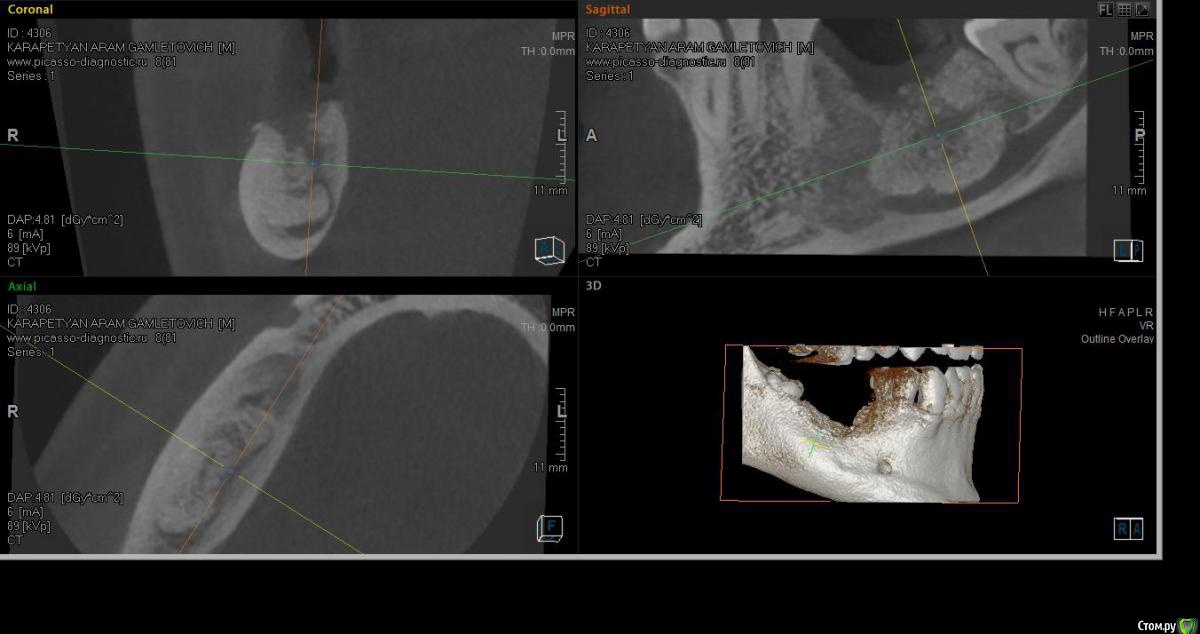

SashaDoc Опубликовано 14 сентября, 2015 Поделиться Опубликовано 14 сентября, 2015 (изменено) Коллеги, нужен совет. Со слов пациента, около 8 мес назад в Армении ему провели операцию по "удалению кисты" н/ч и "засыпали костный порошок" в объеме 6 гр. При мне пациент достал изо рта секвестр 10*5 мм, который он долгое время ощущал языком; во рту - небольшой (3*3мм) дефект слизистой, без отделяемого, в глубине зияет графт. Ничего не болит и не болело.На свежем кт картина не нравится, вопрос - что делать, куда направить? Пациент несколько в стомат теме и понимает, что что-то идет не так, тем более, что врач ему "обещал, что через пол года там кость будет" Изменено 14 сентября, 2015 пользователем SashaDoc Ссылка на комментарий